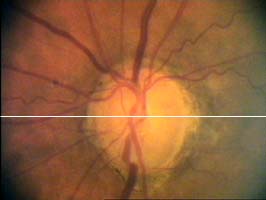

pacientka 1998

(tenze 40-50 torr) Na obrázcích vidíme terče levého oka pacientky, u které se ani opakovanými operacemi nepodařilo snížit nitrooční tlak.

pacientka 2001

Kromě zvětšení a vertikálního protažení exkavace je zřetelné zúžení arterií, zatímco vény jsou zúženy jen méně zřetelně.